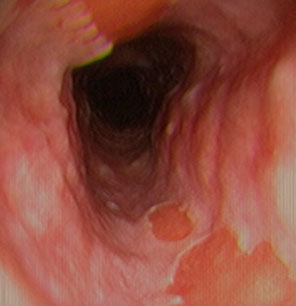

See multiple mucosal rings (linear furrows), esophageal trachealization, feline esophagus, white mucosal specs or normal on endoscopy

Eosinophilic esophagitis